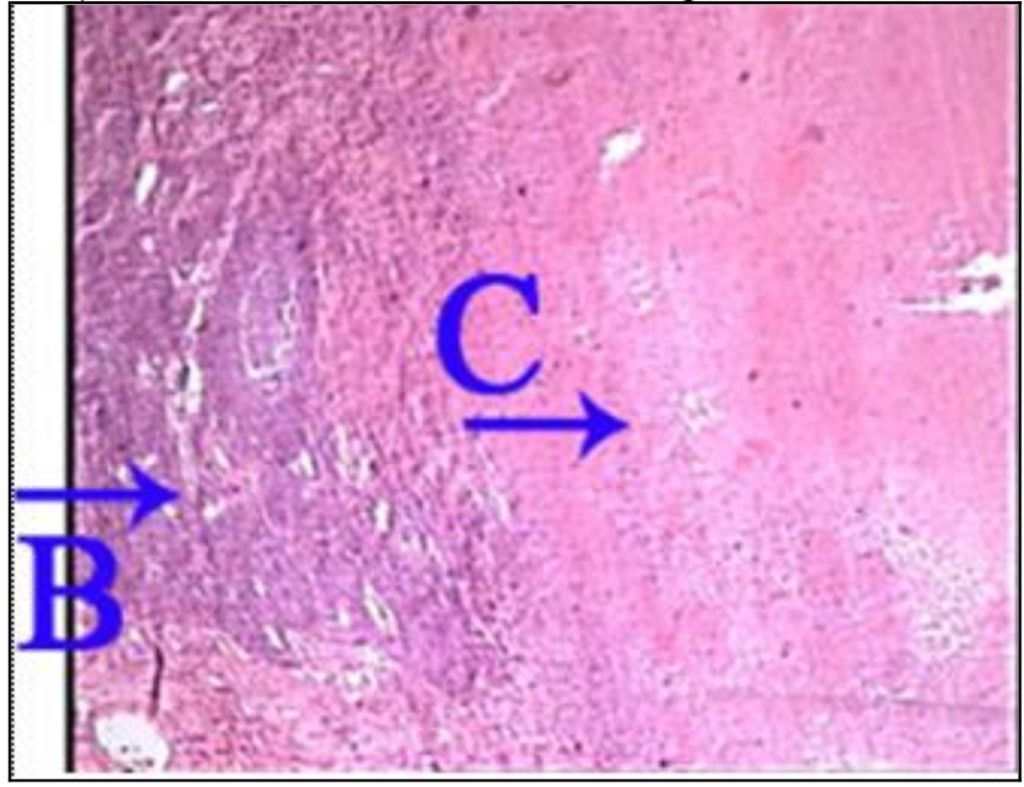

Question 97

Question

What is the correct answer at point A?

Answer

• - bandes scléreuses

• - cellule myocardique survivante

• - tissu conjonctif riche en fibre collagène

• - strie scalariforme

• - striation transversale

Question 98

What is the correct answer at point B?

Question 99

What is the correct answer at point C?

Question 100

What is the correct answer at point D?

Question 101

What is the correct answer at point E?